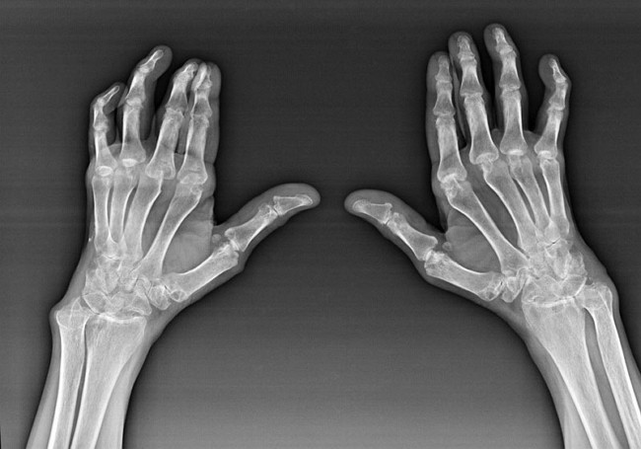

Rheumatoid arthritis

Rheumatoid arthritis is a disease in which the human immune system damages the body's own tissues.In other words, rheumatoid arthritis is an autoimmune pathology.This disease is also systemic as many tissues are affected by it (Muscles, joints, vessels, etc.) and organs (Heart, kidneys, lungs, etc.) in the body.

Despite the fact that rheumatoid arthritis is a systemic disease below it, to a greater extent the joints suffer while the lesion of other tissues and organs is in the background.In this disease, almost all types of brushes may be affected (may be affected (wrists, carpal paths, metacarpal-phalanx, inter -phalax joints).The lesion is usually symmetrical (These.The same joints are affected) On both hands, accompanied by swelling, pain in damaged joints.In the morning, while lifting from the bed, there is some stiffness in the affected joints, which can last about 1 hour and then disappear without a trace.

Quite often with rheumatic arthritis near the affected joints of the brush (More often the piano-fagloga, the inter -phalax joints) Rheumatoid nodes appear.They are a rounded formation located under the skin.On the brush, these entities occur most often on the back.In palpation, they are dense, inactive, painless.The number of them can vary.

Diagnosis of causes of pain in pain

The hands of the pain in the joints of the arm are engaged in the diagnosis and treatment of the causes of pain, mainly a traumatologist and a physician.To diagnose similar causes, these doctors use mainly clinical (History collection, external inspection, palpation and more.), radial (Radiography, computed tomography) and laboratory (General blood test, biochemical blood test, etc.) Examination methods.

When brush injuries, you should consult a traumatologist.The basic diagnostic methods used in medical practice to identify traumatic brush injuries (fractures, dislocations, connections, bruises) are an external examination, anamnesis, radiation methods of examination (Radiography, computed tomography).

Collecting anamnestic data allows the doctor to identify incidents that lead or may cause brush injury.The history of the anamnesis is also used to clarify the symptoms that bother the patient.During an external examination of the brush, it is possible to detect swelling, hematomas, its deformation, restriction of joint mobility.With the help of palpation, the doctor reveals the presence of pain, a violation of the anatomical shape of the joint, damage to the ligaments.Radiation methods of research (Radiography, computed tomography) They allow you to confirm the diagnosis, as during their use the mechanical damage to the anatomical brush formations are clearly visible.